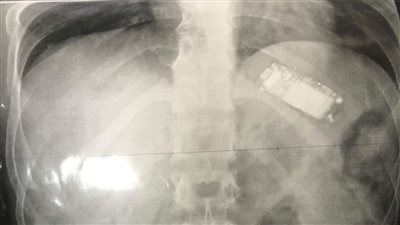

ابتلعه منذ شهرين.. استخراج تليفون محمول من بطن شاب بالمنصورة